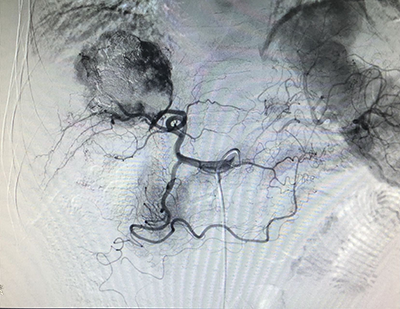

(介入術(shù)中操作)(肝癌的介入治療)